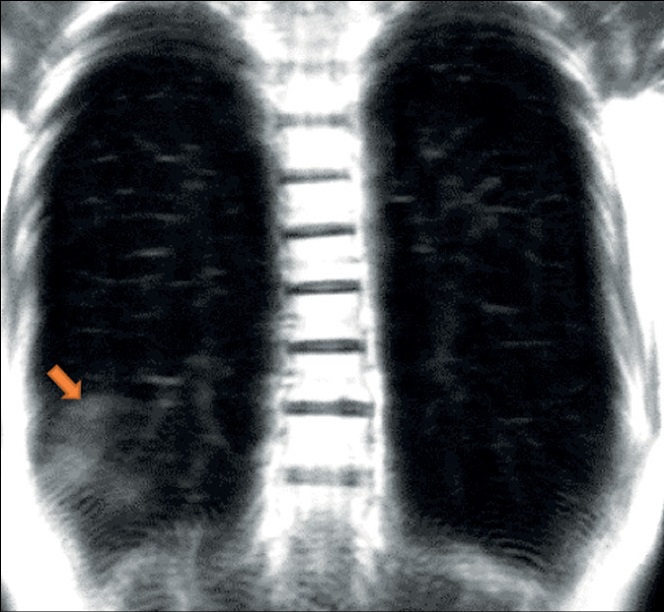

Extensive spread of the coronavirus disease (COVID-19) prompted an investigation of its diagnostic features. Acute viral pneumonia associated with COVID-19 has been described in detail using CT, radiography, and MRI. There is no data in the literature on the descriptive picture observed with dynamic MRI. Considering a comprehensive diagnostic approach, radiologists should know how to correctly recognize and interpret COVID-19 on MRI. This case series demonstrated the ability of dynamic MRI to detect the cloudy sky sign and distinguish it from consolidation in COVID-19 patients, thus presumably distinguishing between early or mild changes and a progressive clinical course. These changes in dynamic lung images on MRI can be recorded depending on the phase of the respiratory cycle. Thus, MRI, as a radiation-free tool that can be used to examine a patient with acute viral pneumonia COVID-19, can be useful in cases where access to computed tomography is limited and dynamic morphofunctional imaging is required.